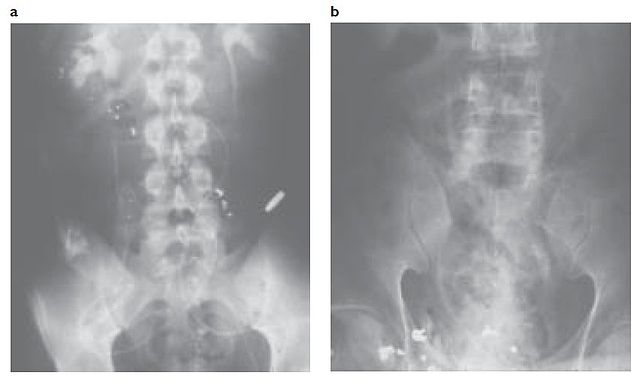

English: Fig. 1-5 (a) The casualty sustained a gunshot wound to the abdomen; this radiograph (b) shows multiple fragments and the retained core from an AK-47 round. The casualty’s injury to the upper urethra was treated with repair and insertion of a stent.

book published in 2005, x-rays made during the Vietnam War era |